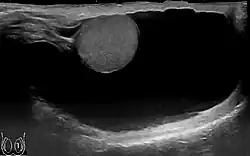

Symptoms of a hydrocele testis can easily be distinguished from testicular cancer, as a hydrocele is soft and fluid-filled, whereas testicular cancer feels hard and rough.[2] A hydrocele is differentiated from a varicocele by physical examination (palpation), and if necessary ultrasound.[3]

Through diagnostic ultrasound the accumulation of fluids can be diagnosed correctly.